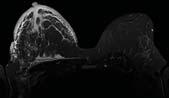

Sex differences could play key role in diagnosing diabetic retinopathy

VANCOUVER – Sex differences could play a key role in diagnosing diabetic retinopathy, according to the results of a groundbreaking study led by Vancouver Coastal Health Research Institute researcher Dr. Ipek Oruc. A condition that puts patients at risk of blindness, diabetic retinopathy may be more likely to progress along a given pathway depending on whether a patient was born male or female.

Diabetic retinopathy is the most common cause of blindness associated with diabetes, affecting around one million Canadians. The condition is characterized by changes to tiny blood vessels at the back of the eye.

In the early stages, symptoms of the disease may go unnoticed, such as with mild to moderate non-proliferative diabetic retinopathy. However, once the condition advances, various vision-threatening complications may arise.

Leakage from damaged blood vessels can lead to eye swelling – called macular edema – which causes vision loss primarily affecting central vision.

“Regular monitoring is crucial for detecting early signs of diabetic retinopathy and to prevent its progression to moderate or severe disease,” said Oruc. “However, aside from considerations during pregnancy – when females are at higher risk for progression – sex is not presently factored into disease diagnosis, management or treatment.”

Researchers trained, validated and tested an artificial intelligence (AI) algo-

rithm on a data set of 2,967 fundus images from 1,491 female and 1,476 male patients with diabetic retinopathy. The fundus is the inner area at the back of the eye comprising the retina, optic disc, fovea, macula and blood vessels.

The algorithm was trained to classify patient sex from retinal images of people with diabetic retinopathy. Male and female groups were matched for age, ethnicity, severity of diabetic retinopathy and hemoglobin A1c levels – a measure of blood sugar in the body – to prevent the model from using these potentially confounding variables when classifying a patient’s sex.

Oruc and her team used convolutional neural networks (CNNs) – AI algorithms specializing in image classification – to identify patterns of diabetic retinopathy presentation in the images. This approach

builds on the team’s prior research on the classification of retinas by sex.

One of the research team’s central objectives was to find an empirical method to identify potential differences in how diabetic retinopathy manifests in females and males.

To see whether there were sex-specific disease characteristics of diabetic retinopathy, Oruc and her team used Guided GradCAM saliency maps – an explainable-AI technique that can peer into the often mysterious ‘black box’ of CNNs. While CNNs can identify unique features in a series of images, the explanatory AI built into Guided Grad-CAM saliency maps helps researchers understand how the CNN arrived at its conclusions.

“For example, if we were to use explainable AI to identify what distinguishes a celebrity from other people, it may high-

light the celebrity’s nose and mouth as important features that set that celebrity apart,” Oruc said.

The Guided Grad-CAM saliency maps showed that the CNN focused on the macula in female fundus images and the optic disc and peripheral branching vasculature from the optic nerve in male fundus images.

“This pattern differed noticeably from the saliency maps generated by CNNs trained on healthy eyes, which did not highlight these particular regions, indicating that diabetic retinopathy may manifest differently by sex,” said Oruc.

“However, further research is needed to validate this hypothesis,” she adds, which is why her team is presently conducting a follow-up study.

The research team’s application of CNNs – interpreted using Guided Grad-CAM –was able to achieve a high level of accuracy using a smaller dataset for training the algorithm than is typical, Oruc noted. “This is particularly important, as large datasets are more costly and time-consuming.”

“The success of this approach with a small dataset puts studies like ours within reach of other research teams with limited resources.”